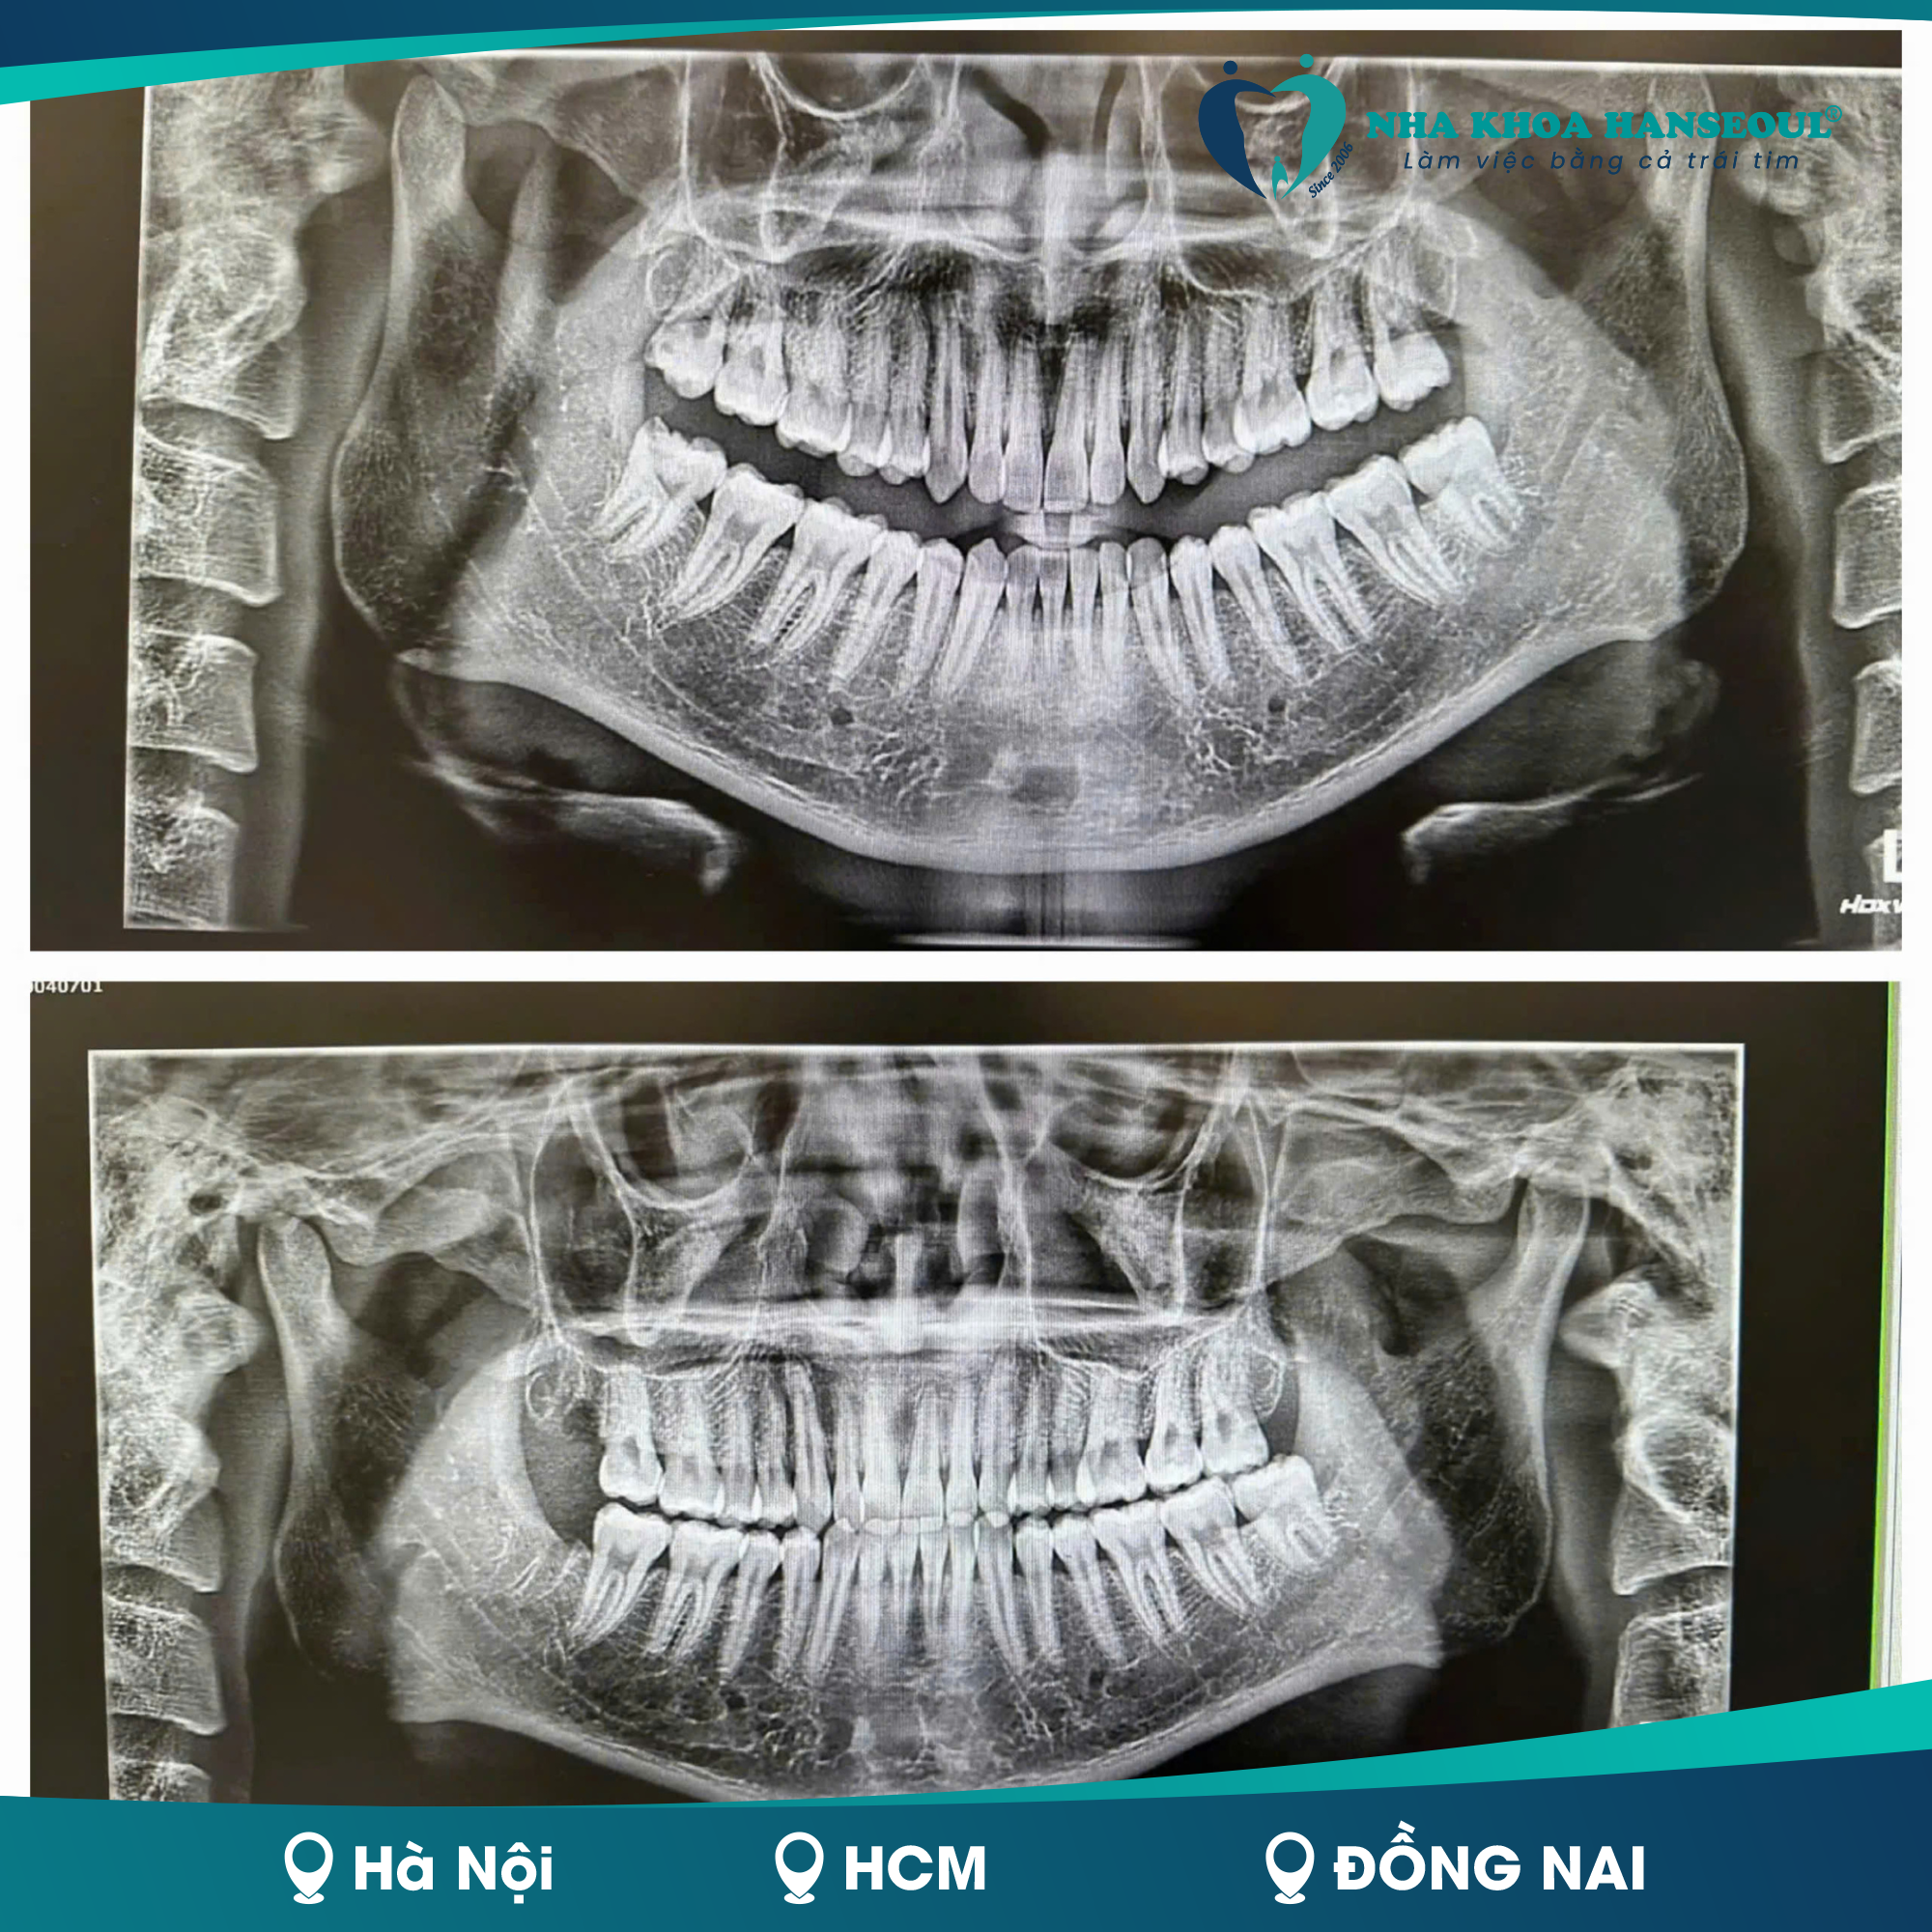

Mọc Răng Số 8 Có Đau Không? Dấu Hiệu Nhận Biết Và Giải Pháp Hiệu Quả

25/06/2025